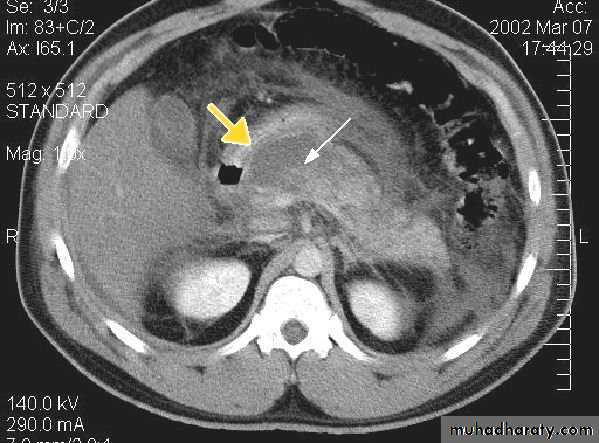

Cirrhosis of the liver and portal hypertension

In portal hypertension, the pressure in the portal venous system is elevated due to obstruction of the blood flow in the portal or hepatic venous system. Cirrhosis is the commonest cause. Other causes include the occlusion of the hepatic veins (Budd-chiari syndrome) and thrombosis of the portal vein following infection of the umbilical vein in neonates or secondary to acute pancreatitisThe signs of liver cirrhosis at CT and US are :

1.reduction in size of the right lobe of the liver2.irregularity of the surface of the liver

3.splenomegaly

4.ascites

5.coarse abnormal liver texture at US while at CT, the parenchyma appears normal until late in the disease.

Patency of the splenic, portal & hepatic veins can be assessed with Doppler US,CT&MRI

Liver trauma

Trauma to the liver is the commonest abdominal injury that leads to death, with parenchymal lacerations are the most frequent injury, often accompanied by subcapsular and intrahepatic hematoma.US has become part of the standard assessment. Focused Assessment with Sonography for Trauma "(FAST scan) is a rapid bedside examination which examines four areas for free fluid:

1.perihepatic and hepatorenal space

2.perisplenic

3.pelvis

4.pericardium

CT is more sensitive and specific. Lacerations and hematomas are recognized as low density areas relative to the normal intact, enhanced parenchyma. Leakage of contrast indicate active bleeding